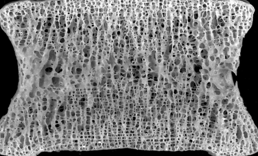

正常骨质

骨质

骨质疏松(轻)

骨质疏松(重)

骨质疏松症是一种由多种原因引发的全身性骨病,主要特征是骨密度和骨质量下降,骨微结构损害,使骨脆性增加,形成易发生骨折的状态。骨质疏松症主要分为原发性和继发性,原发性又分为绝经后骨质疏松(Ⅰ型)、老年性骨质疏松症(Ⅱ型)和特发性骨质疏松。